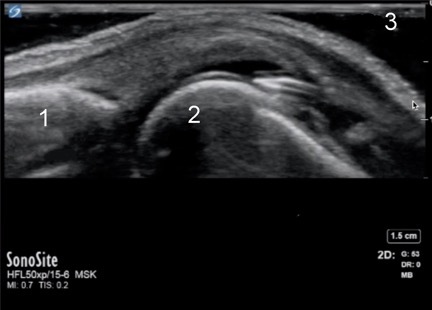

Hand MCP Joint Needle Placement- Aspiration Injection Image

1. Proximal Phalanx

2. Distal Metacarpal Head

3. Sterile Gel